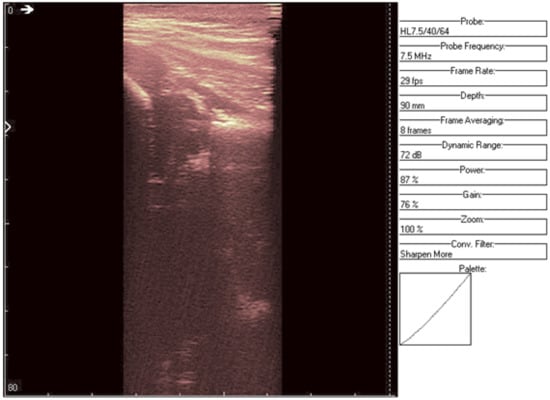

The original recording is displayed in Figure 3. As a first processing step, a color palette has been added to the original ultrasound in order to better highlight the noise and noise-free zones (Figure 4). The wavelet-based filter, as described in Section 2, is applied, and the processed image is shown in Figure 5.

We can remark, when analyzing the zoomed parts of Figure 4 and Figure 5 (the acetabulum), that in the original image speckle noise appears, strongly affecting the image. The filtering system proposed in this paper does not completely remove the speckle but brightens the image, at the same time not oversmoothing the original image. The main bone structure can be better outlined. A comparison between the same zoomed region of interest in the original image and denoising result, showing the disappearance of the speckle grains (Figure 6)—resulting thus in a smoother image where anatomical features can be better outlined.

Figure 4. Original data with an added color palette. A region of interest containing some speckle grains was encircled in yellow.